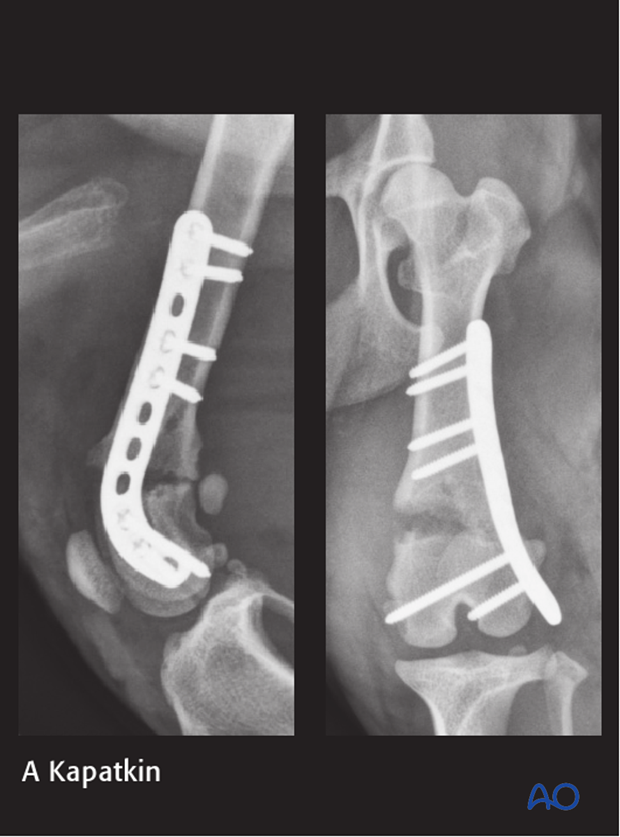

2-year-old small mixed breed dog presented from a shelter after being hit by a car, with a left grade 1 open 33-A1 fracture, comminuted acetabular fracture, and sacroiliac luxation.

The fracture was repaired using a reconstruction plate and a K-wire. Note the transcondylar distal screw placement.

A femoral head and neck excision was also performed.

The patient reportedly recovered well on telephone follow up but never returned for radiographs.